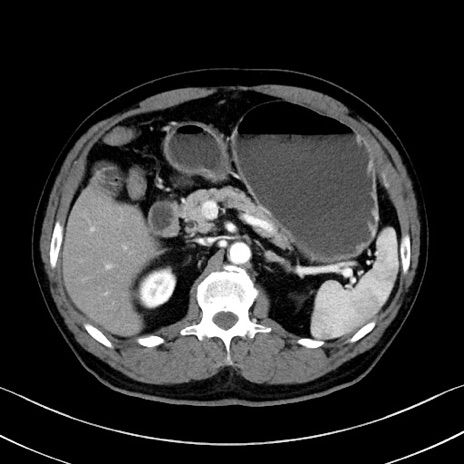

症例35(横断像)

【症例】70歳代 男性

【主訴】腹部膨満、嘔吐

【現病歴】昨日より腹部膨満感出現。本日増悪し、仙痛出現。嘔吐あり、受診。

【既往歴】糖尿病、胆摘後

【身体所見】BP 149/80mmHg、HR 74/min、BT 35.9℃、腹部:膨満、軟、圧痛なし。腸雑音減弱あり。上腹部正中切開瘢痕あり。

【データ】WBC 13500、CRP 1.72